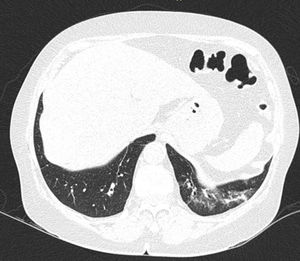

En la EPI se produce disminución de la impedancia acústica entre el aire pulmonar y los tejidos blandos de la pared torácica, porque parte del espacio inicialmente ocupado por el volumen de aire es sustituido por infiltración de células inflamatorias o tejido conectivo, provocando la aparición de alteraciones en la línea pleural y artefactos verticales llamados «líneas B». Las líneas B son indicativas de aumento de la densidad pulmonar subpleural antes de la consolidación y pueden estar causadas por la existencia, aunque no exclusivamente, de enfermedad intersticial25. La línea pleural se vuelve irregular y engrosada y puede aparecer borrosa y fragmentada. Las líneas B se muestran como artefactos verticales en forma de rayo hiperecoico que surgen de la línea pleural y se extienden hasta el final de la pantalla sin desvanecerse, borran las líneas A y se mueven sincrónicamente con el deslizamiento pleural. La presencia de múltiples líneas B es el signo ecográfico que define al «síndrome intersticial»26. En la figura 2 se muestra la TACAR de un paciente con AR y EPI; en la figura 3, los hallazgos de ultrasonido.